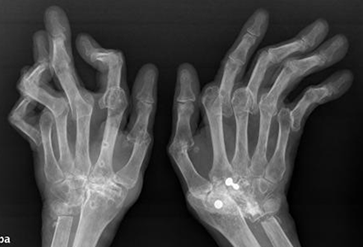

Fig 24 A. Artropatía reumática.

Rx AP. Enfermedad avanzada con osteoporosis, disminución simétrica del espacio articular y deformidad.

Fig 24 B. Artropatía reumática.

Rx AP. Enfermedad avanzada en la mano, con osteoporosis periarticular, disminución de los espacios articulares interfalángicos, radio y ulnocarpiano y fusión de los huesos del carpo.

Fig 25. Artropatía reumática.

Rx AP. Enfermedad muy avanzada, con sub y luxación de articulaciones metacarpofalángicas. Reabsorción y cambios PostQx en los huesos del carpo y el tercio distal de los cúbitos.